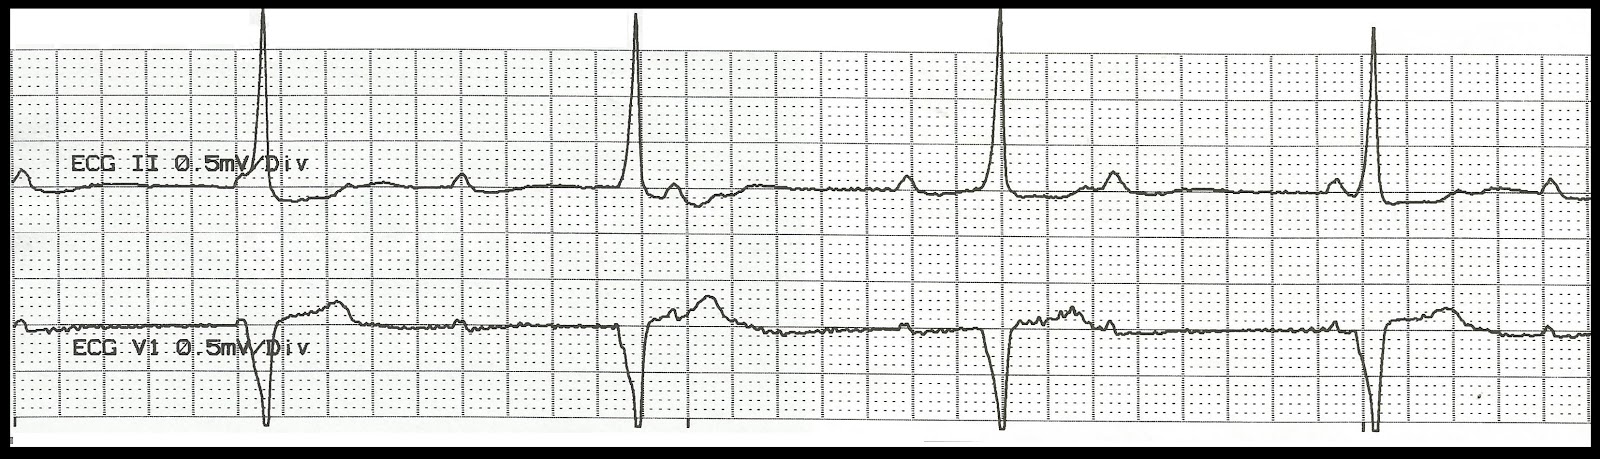

| Normal sinus rhythm with unifocal PVCs |

The rhythm is irregular due to the presence of the PVCs. The rate is 80/min. The P waves are associated with a QRS complex. There are two unifocal PVCs. The P wave following the PVCs have a PR interval of .20 sec. which is longer than the sinus beats. PR: .16 sec, QRS: .08 sec, QT: .40 sec